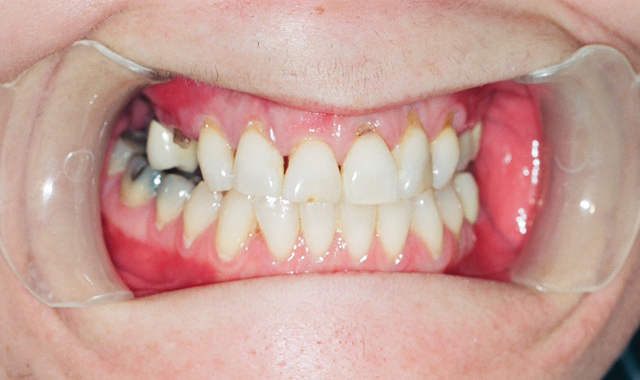

Blackened, rotted, crumbling and broken teeth are just a few of the tell-tale signs that your patient may be using methamphetamine (Fig. 1).

Fig. 1

When they do present to our dental offices, users are often embarrassed by their drug use, concerned about their unattractive smiles and overwhelmed with dental pain. Similarly, as dentists, we may feel overwhelmed by the magnitude and severity of their dental problems and our own uncertainty about which aspects of treatment (surgical, restorative, prosthetic, prevention) to prioritize and initiate.